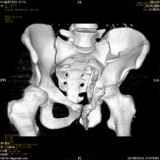

Уважаемые коллеги! Хотелось бы услышать совет по тактике лечения представлленого больного.Поступил после лечения в одном изотделений области. Травма 2,5 месяца назад. После выведенияиз шока был произведен остеосинтез перелома бедра, предплечья, до перевода к нам проводилосьвытяжение по оси шейки бедра за стержень, введенный в большой вертел. На сегодня деформацияригидна, клинически мобильности не определяется. Заранее признателен. P.S. Данный вид травм не включен в перечень "высокотехнологичных операций", направить длялечения по квотам Минздрава очень сложно.

Это обзорные и косые снимки

Привет, Леонид. Оскольчатый высокий двухколонный перелом в такие сроки трогать не надо, т.к. это про такие переломы сказано: "кто с ножом на Ж. пойдет тот в ней и останется...".